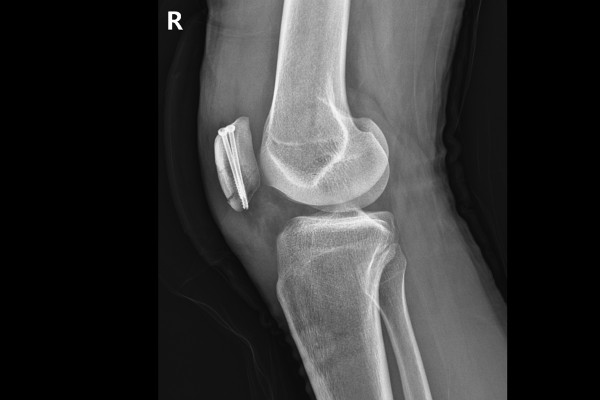

환자분의 상태를 자세히 확인하기 위해 X-RAY와 MRI를 촬영하였습니다. X-RAY 촬영 결과 슬개골에 골절선 2개가 확인됩니다.

9f695db682e5f1ea0b431dfdec73e7ff_1766564241_3382.jpg